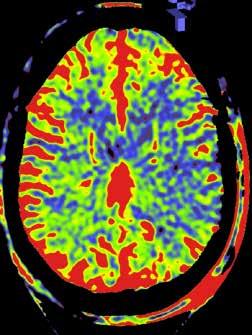

Om het probleemgebied duidelijk in kaart te brengen, werd uitgewe ken naar een perfusiescan die via contrastvloeistof de doorbloeding van de hersenen in beeld brengt. Menovsky: ‘We interpreteren de beelden altijd samen met de radioloog. Vanuit hun vakgebied zien ze dingen die wij niet zien, en omgekeerd.’ Op de beelden was te zien dat een bepaald deel van

Op het linkerbeeld is te zien dat de bloedvaten in de hersenen meer moeite hebben om de bloedtoevoer in de hersenen te garanderen. Op het beeld rechts, na de operatie, is het probleem hersteld.

de hersenen onvoldoende door bloed was. ‘Op basis daarvan was een bypass de beste behandeling. Tijdens een operatie maakten we een luik in de schedel en verbonden we een slagader van de huid met het deel van de hersenen dat onvol doende doorbloed was. Dat heeft het probleem opgelost voor die patiënt. Met dank aan de precieze beelden. Zonder die beelden was de ingreep nooit mogelijk geweest.’